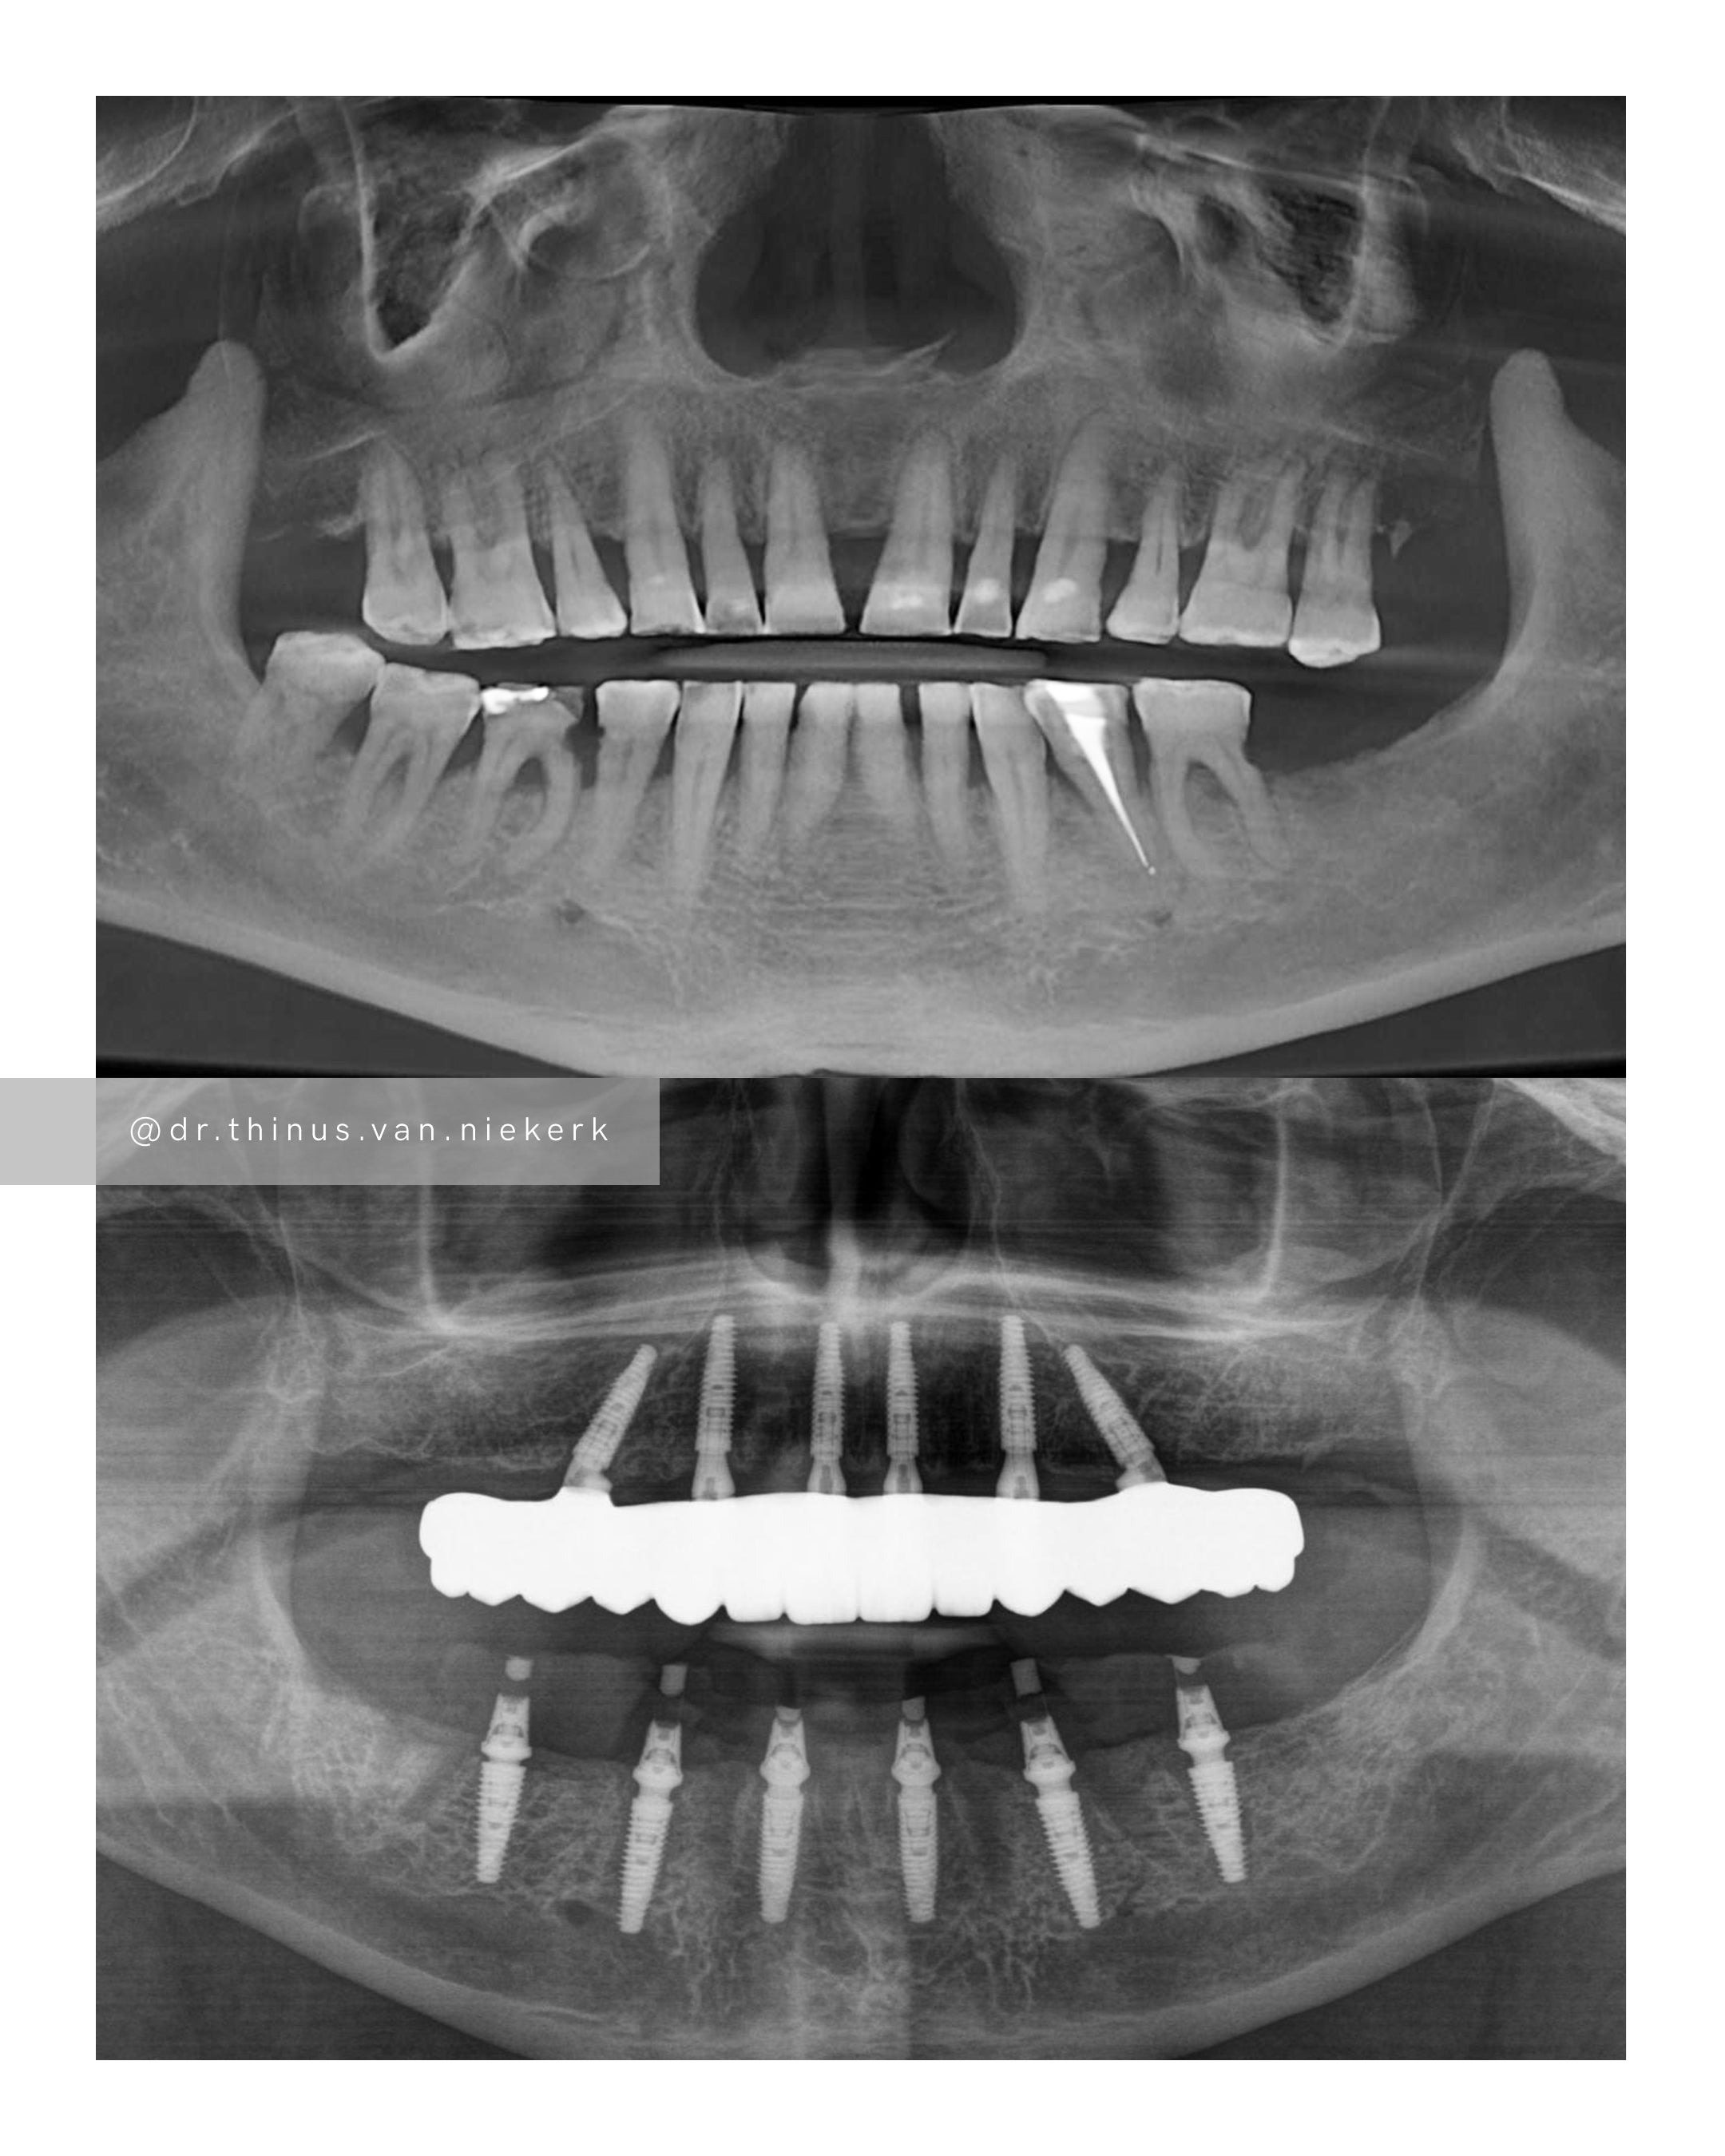

TREATMENT OBJECTIVE

Our aim was to remove all elements of infection and disease and to restore function as quickly as possible. The complete case was digitally planned prior to the day of surgery. Six fully-guided implants were placed during a two-hour morning surgery. An immediate implant-supported prosthesis was delivered on the same day.

COMMENTS

This case demonstrated the power and effectiveness of digital implant-surgery planning and CAD design software.